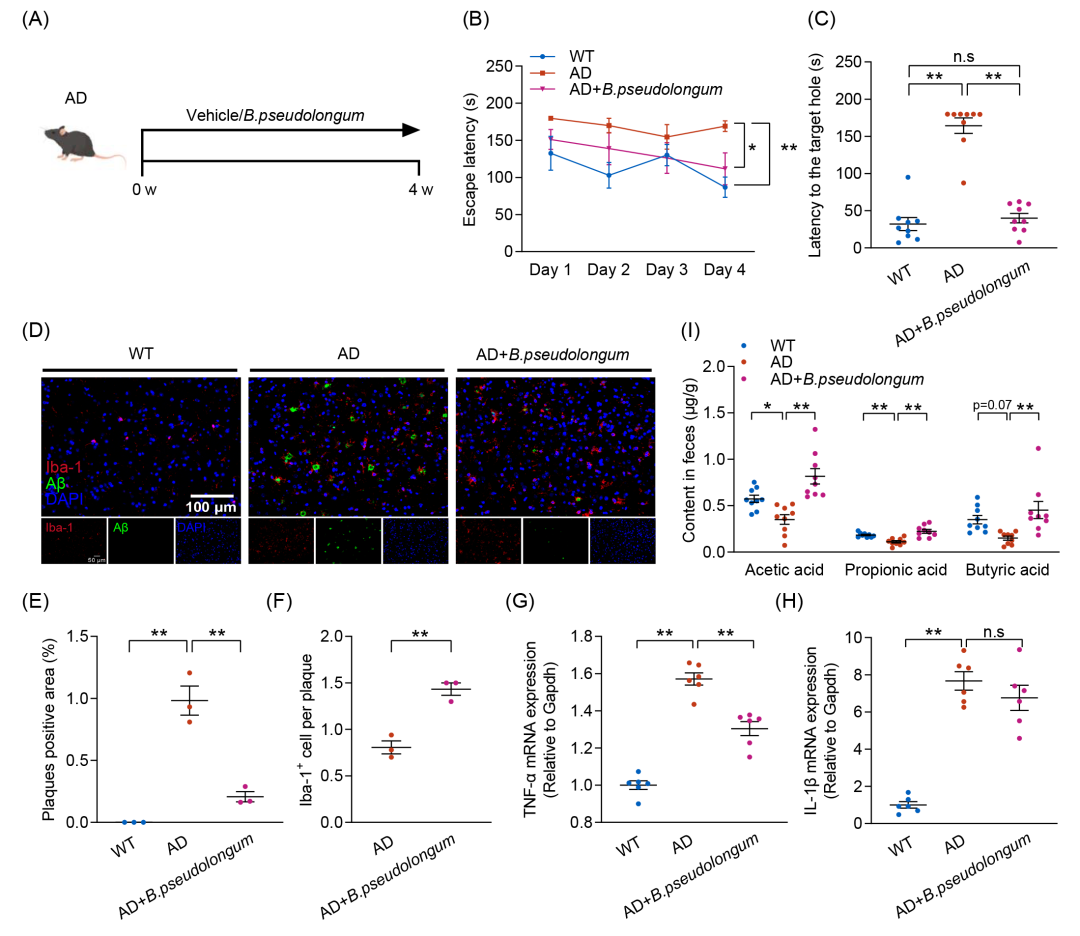

鉴于肠道菌群在TRF介导的AD认知功能障碍缓解过程中发挥着不可替代的作用,以及TRF诱导的B. pseudolongum丰度显著增加与AD病理生理学相关生物功能参数的改善密切相关,本研究进一步探讨了4周口服B. pseudolongum干预对AD小鼠认知障碍的影响(图4A)。正如预期的那样,B. pseudolongum干预显著改善AD小鼠的认知功能,表现为逃避潜伏期(图4B)、到达目标孔的潜伏期(图4C)和接近目标孔的次数(图S6D)的显著降低。此外,B. pseudolongum干预减少了AD小鼠脑内Aβ积累,并增加了Aβ斑块周围的Iba-1+小胶质细胞的聚集(图4D-F和图S6D-F)。此外,B. pseudolongum干预还显著降低了TNF-α水平,但对IL-1β的表达没有产生影响(图 4G、H)。与先前的研究一致,B. pseudolongum可促进SCFAs的产生。本研究观察到B. pseudolongum的相对丰度与粪便PA水平之间存在相关性,而TRF进一步增强这种相关性。值得注意的是,B. pseudolongum干预显著恢复了AD小鼠粪便中乙酸、PA和丁酸的水平,而这些代谢产物在AD小鼠中均明显下降(图4I)。这些结果表明,TRF诱导B. pseudolongum丰度增加,该菌与认知功能改善密切相关,并能够通过促进SCFAs生成,在缓解AD认知功能障碍及病理损伤方面发挥与TRF相似的作用。

图4. B.pseudolongum干预缓解AD小鼠的认知损伤

(A)每组接受B.pseudolongum或生理盐水干预的实验流程示意图(n = 9);(B)逃避潜伏期;(C)到达目标孔的潜伏期;(D)小鼠皮层中Aβ沉积(绿色)及Iba-1+阳性小胶质细胞(红色)的免疫荧光染色图像(n = 3)(比例尺:100 μm);(E)Aβ斑块阳性区域的定量分析;(F)Aβ斑块相关小胶质细胞的定量分析;(G)TNF-α的mRNA水平测定(n = 6);(H)IL-1β的mRNA水平测定(n = 6);(I)粪便短链脂肪酸水平(n = 9)。数据以均值 ± SEM表示。*p < 0.05,**p < 0.01;one-way ANOVA结合Tukey多重比较检验。